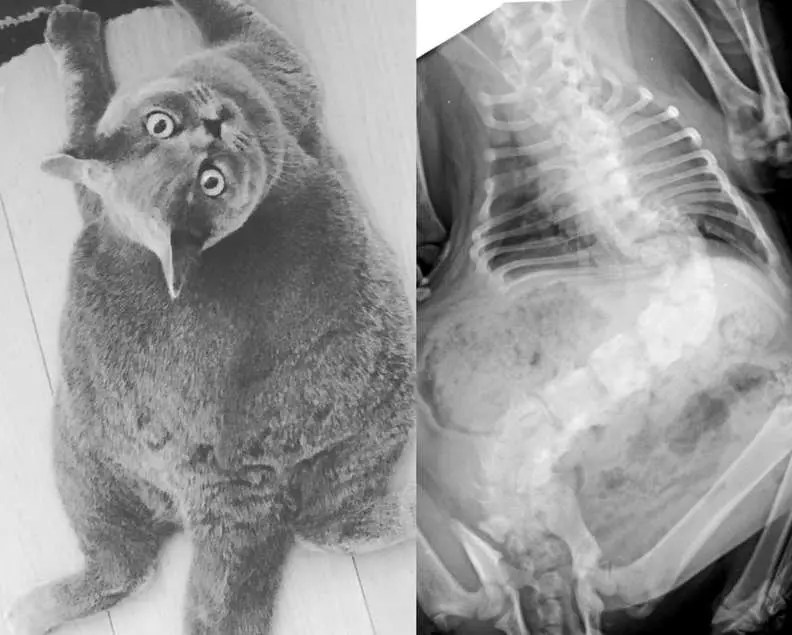

My mother has untreated scoliosis and i was treated for scoliosis as a 12 year old child. How to treat colitis in cats naturally? Scoliosis (a lateral curvature of the spine) is also an easily visible form of vertebral malformation.

It's a tough situation, i think 12 is too young for a cat, especially the playful siamese. Oftentimes, no treatment is needed, as long as your dog isn’t in pain. Scoliosis is an abnormal lateral curvature of the spine.